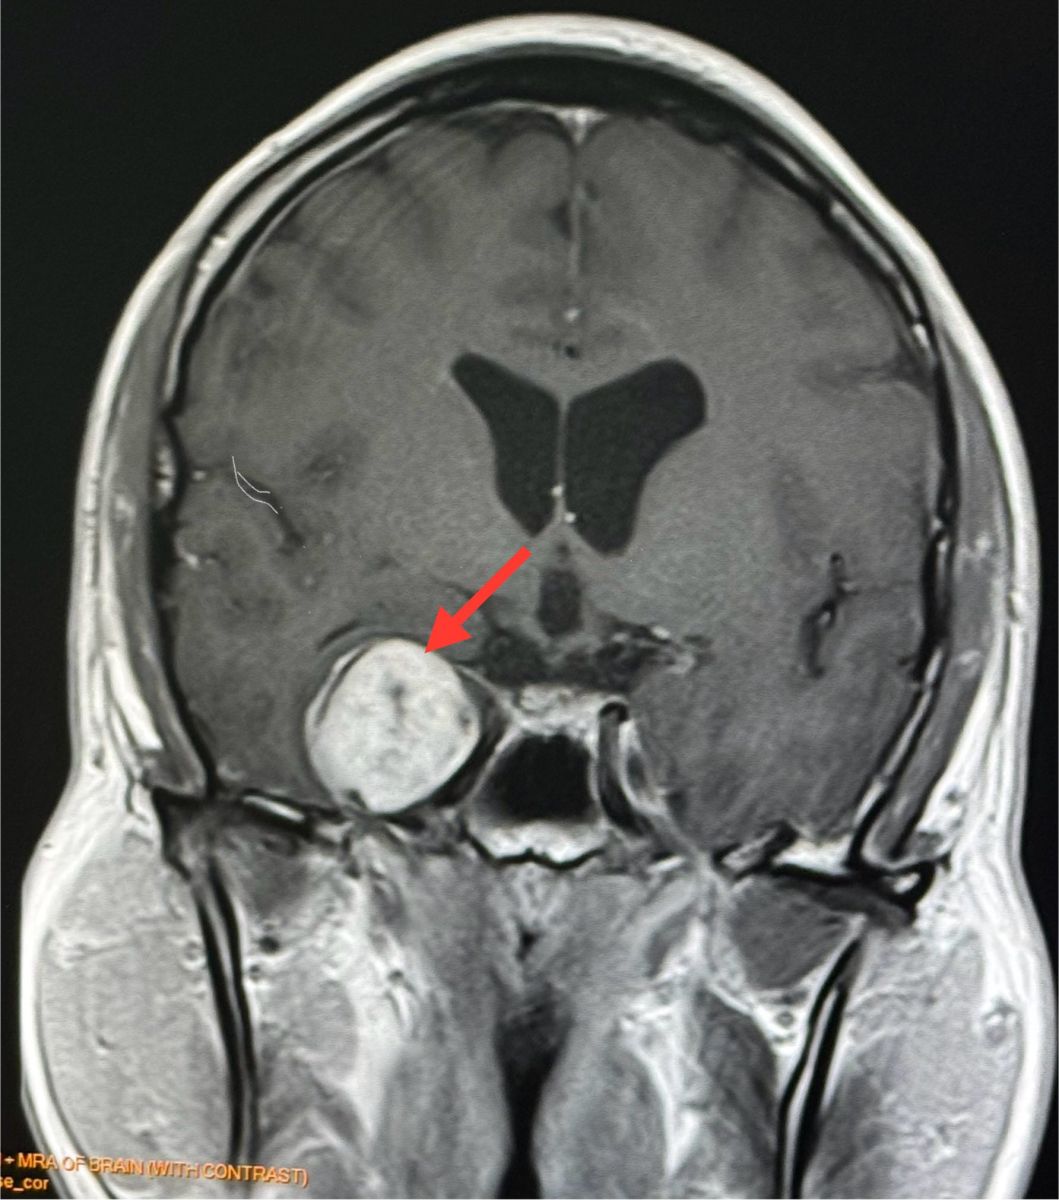

ทำคอมพิวเตอร์ CT สมองพบก้อนขนาด 2.7 × 3.0 × 2.9 เซนติเมตร ที่กลีบขมับของสมองด้านขวา right temporal lobe ทำ MRI (Magnetic Resonance Imaging) โดยใช้คลื่นแม่เหล็กไฟฟ้าและคลื่นวิทยุความถี่สูงและฉีดสี พบก้อนขนาด 3.1 × 2.9 × 2.9 เซนติเมตร สงสัย Trigeminal Schwannoma เนื้องอกของปลอกประสาทเส้นประสาทสมองเส้นที่ 5 ข้างขวา

Trigeminal Schwannoma คือเนื้องอกชวานโนมาที่เกิดจากเซลล์ชวานน์ (Schwann cells) ซึ่งเป็นเซลล์ที่ทำหน้าที่สร้างเยื่อไมอีลินที่ห่อหุ้มเส้นประสาท โดยเนื้องอกชนิดนี้เกิดขึ้นบริเวณเส้นประสาทไทรเจมินอล ซึ่งเป็นเส้นประสาทสมองเส้นที่ 5 เนื้องอกชนิดนี้พบน้อยมากๆ ส่วนใหญ่เป็นเนื้องอกไม่ร้ายแรง (benign) โตช้า รักษาด้วยการผ่าตัด หรือฉายแสง